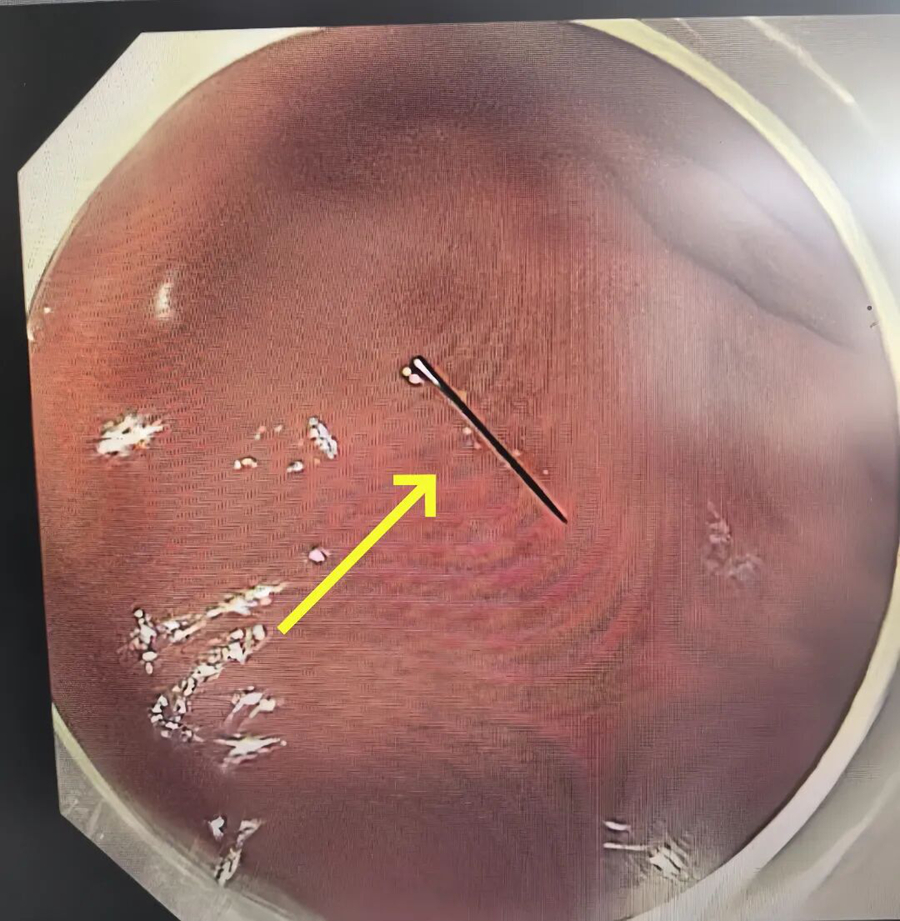

凌晨 3 点,术前准备就绪,一场全麻下胃镜异物取出术正式开始。凭借丰富的儿童内镜经验,手术仅用 10 余分钟就顺利完成,那截约1 厘米长的断针被完整取出。

万幸的是,断针尚未刺破胃黏膜、未造成出血损伤。当医生将取出的断针展示在家人面前时,一直悬着的心终于落地。